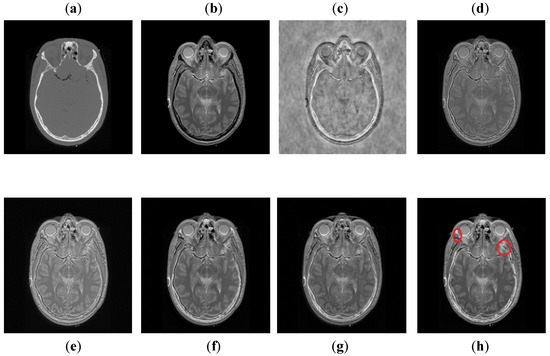

It can be visually observed in Figure 9 that the DCT method has more artifacts that distort the overall quality of a fused image. The DWT and NSST-SF-PCNN produce almost similar results, but DWT has more contrast and less noise than NSST-SF-PCNN. However, both methods have poor detailed and structured information that significantly loses valuable information about soft tissues. The CSR method effectively captures more information from the CT image, but due to non-uniform illumination, it drastically fails to restore more information about soft tissues from MRI image. On the other hand, the CNN method retains most of the information about soft tissues from an MRI image with good contrast, but it cannot completely capture edges and boundaries from a CT image that affect the image quality. The proposed method shows its superiority over other methods by producing a fused image that contains information from both source images. It has better contrast with very negligible artifacts. Additionally, it can be further explored from red boxes that the proposed method can effectively retain the soft tissues from MRI image and preserve bright and sharp detail about bones from a CT image.

Figure 9. Data-3: (a) CT image, (b) MRI image, (c) DCT, (d) DWT, (e) NSST-SFT-PCNN, (f) CSR, (g) CNN, and (h) Proposed.